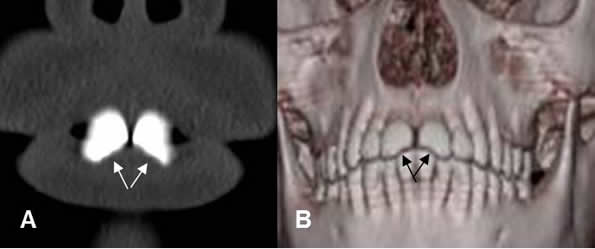

Fig 76. Fracturas dentales.

A: TAC reconstrucción coronal y B: TAC reconstrucción 3 D. Trauma directo, que produjo fractura en la parte medial, de ambos incisivos. (Flechas).